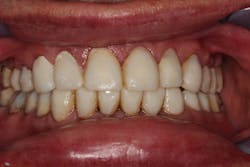

Chris returned for us to cement the crowns. The lab had fabricated exquisite-looking crowns that function properly (figures 7–9). We prepped the uppers in one day, lowers in another day, and cemented all in one day.

Figure 7: Final crowns

Figure 8: Final crowns

Figure 9: Final crowns

I checked for fit and fine-tuned the patient’s bite with T-Scan (Tekscan), and Chris has been smiling ever since.